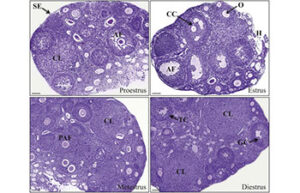

- Determining the reproductive cycle of mice and rats